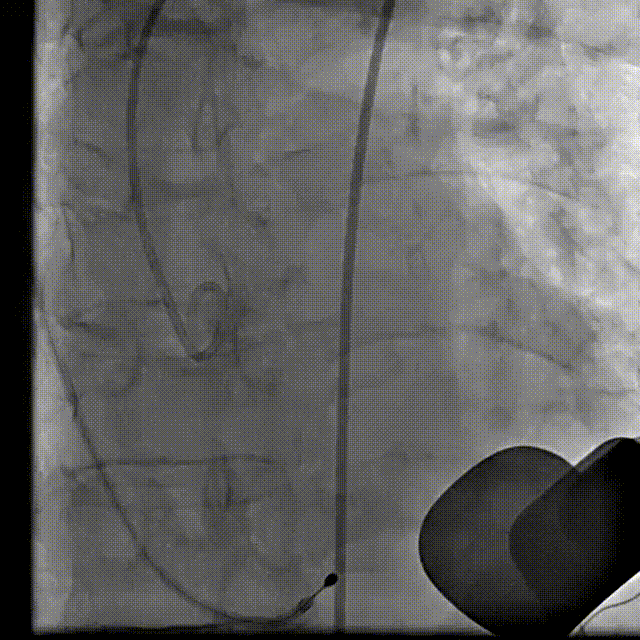

瓣膜交界对齐释放

22 mm球囊后扩

最终造影

术后即刻TEE示:主动脉瓣膜峰值血流速为1.2m/s,最大压差为5mmHg,平均压差为2mmHg。未见明显人工主动脉瓣反流及瓣周漏。